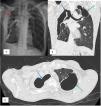

Tracheopleural fistula is an extremely rare complication of chronic pulmonary tuberculosis as no similar case being published previously. A 52-year-old gentleman with history of chronic pulmonary tuberculosis (PTB) 20 years ago was presented with lethargy for 2 weeks associated with occasional haemoptysis. There was loss of weight and loss of appetite. No fever, shortness of breath, chest pain or night sweat. On examination, he was pale, afebrile, normotensive and not tachycardic. There was reduced air entry on the right lung with generalized coarse crepitations. Chest radiograph (Fig. 1a) showed right pneumothorax. Contrast-enhanced CT Thorax (Fig. 1b and c) confirmed presence of tracheopleural fistulae with thick-walled right pneumothorax. He was given intravenous (IV) tranexamic acid, blood transfusion and metered-dose inhaler (MDI) berodual and spiriva. He was stable under room air and discharged well after 5 days. He was planned for optimization of medical treatment as he refused surgical intervention or bronchoscopy. Chest tube was not done due to patient's refusal and clinically the oxygen saturation was acceptable. Tracheopleural fistula is rare and usually seen among cancer patients after chemotherapy.1 As opposed to tracheopleural fistula, tuberculous bronchopleural fistula is commonly seen although both conditions are rare.2 Clinical manifestations are varied among individuals and direction of treatment should be tailored individually to achieve good quality of life.

Chest radiograph showed right pneumothorax with pleural thickening (red arrow) (a). CECT Thorax in coronal (b) and axial (c) views revealed tracheal wall defects with direct communication with the pleural cavity, representing tracheopleural fistula (blue arrows). Left upper lobe lung bullae (green arrows) (b, c).